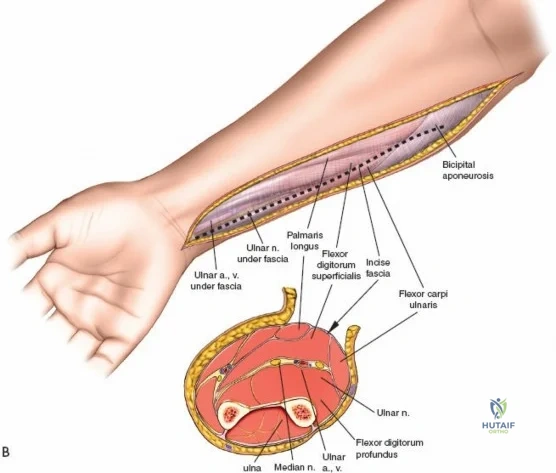

Superficial Surgical Dissection and Internervous Plane

Incise the deep fascia of the forearm in line with the skin incision. The initial goal is to identify the medial border of the brachioradialis as it courses down the forearm. It is a common pitfall to search for this border too far laterally. At the level of the elbow, the brachioradialis is expansive and extends almost halfway across the anterior forearm. It is surprisingly easy to mistake the plane between the brachioradialis and the extensor carpi radialis longus for the correct intermuscular plane.

To confirm the correct plane, look for the superficial branch of the radial nerve. This sensory nerve runs on the undersurface of the brachioradialis muscle. Once the true medial edge of the brachioradialis is found, develop the plane between it and the pronator teres (proximally) or the flexor carpi radialis (distally). Retract the brachioradialis laterally, taking care to keep the superficial radial nerve attached to its undersurface to protect it from traction injury.

Managing the Radial Artery and Recurrent Leash

As the brachioradialis is retracted laterally, the radial artery and its venae comitantes are exposed lying deep in the middle part of the forearm, closely related to the medial edge of the wound. Begin dissection distally and work proximally. Just below the elbow joint, the radial artery gives off the recurrent radial artery and a leash of muscular branches that dive laterally into the brachioradialis.

This leash must be meticulously managed. Take time to isolate, ligate, and divide these vessels. Do not attempt to use electrocautery alone on the larger branches, and absolutely avoid blunt avulsion. Avulsion of these vessels from the main radial artery is a potent cause of difficult-to-control intraoperative bleeding and severe postoperative hematoma. Once the leash is divided, the brachioradialis can be fully mobilized laterally, exposing the deep muscular layer.

Deep Surgical Dissection: Exposing the Proximal Third

Exposing the proximal third of the radius requires extreme vigilance due to the proximity of the posterior interosseous nerve. The key anatomical landmark here is the insertion of the biceps tendon. Follow the biceps tendon distally to its insertion on the bicipital tuberosity of the radius. A small bursa lies just lateral to the tendon; incise this bursa to gain initial access to the proximal radial shaft. Because the radial artery lies superficial and medial to the tendon at this level, all deep dissection must remain strictly lateral to the biceps tendon.

The proximal radius is draped by the supinator muscle. The PIN passes directly through the belly of the supinator. To protect the nerve, the forearm must be fully supinated. Supination dynamically rotates the radius, carrying the insertion of the supinator anteriorly and simultaneously displacing the PIN laterally and posteriorly, safely away from the surgical field.

With the forearm fully supinated, identify the broad insertion of the supinator on the anterior aspect of the radius. Incise the supinator directly along the line of its insertion onto the bone. It is critical to detach the muscle by dividing its insertion sharply at the bone, rather than splitting the muscle belly, which would risk cutting the PIN.

Proceed with strict subperiosteal dissection, elevating the supinator laterally off the bone. This is one of the rare instances in orthopedic surgery where the safety gained by staying in a subperiosteal plane completely outweighs the theoretical vascular damage to the bone caused by periosteal stripping. The elevated supinator muscle belly now acts as a protective cushion for the PIN.